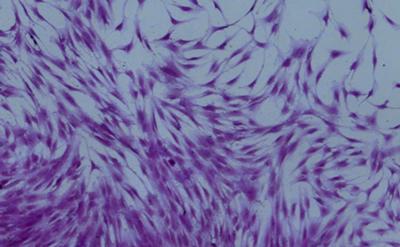

In laboratory tests, the researchers used gold nanoparticles – tiny spherical particles made up of thousands of gold atoms – coated with oligonucleotides (strands of DNA), to optically detect the specific messenger RNA (mRNA) signatures of skeletal stem cells in bone marrow. When detection takes place, the nanoparticles release a fluorescent dye, making the stem cells distinguishable from other surrounding cells, under microscopic observation. The stem cells can then be separated using a sophisticated fluorescence cell sorting process.

Stem cells are cells that are not yet specialised and can develop to perform different functions. Identifying skeletal stems cells allows scientists to grow these cells in defined conditions to enable the growth and formation of bone and cartilage tissue – for example, to help mend broken bones.